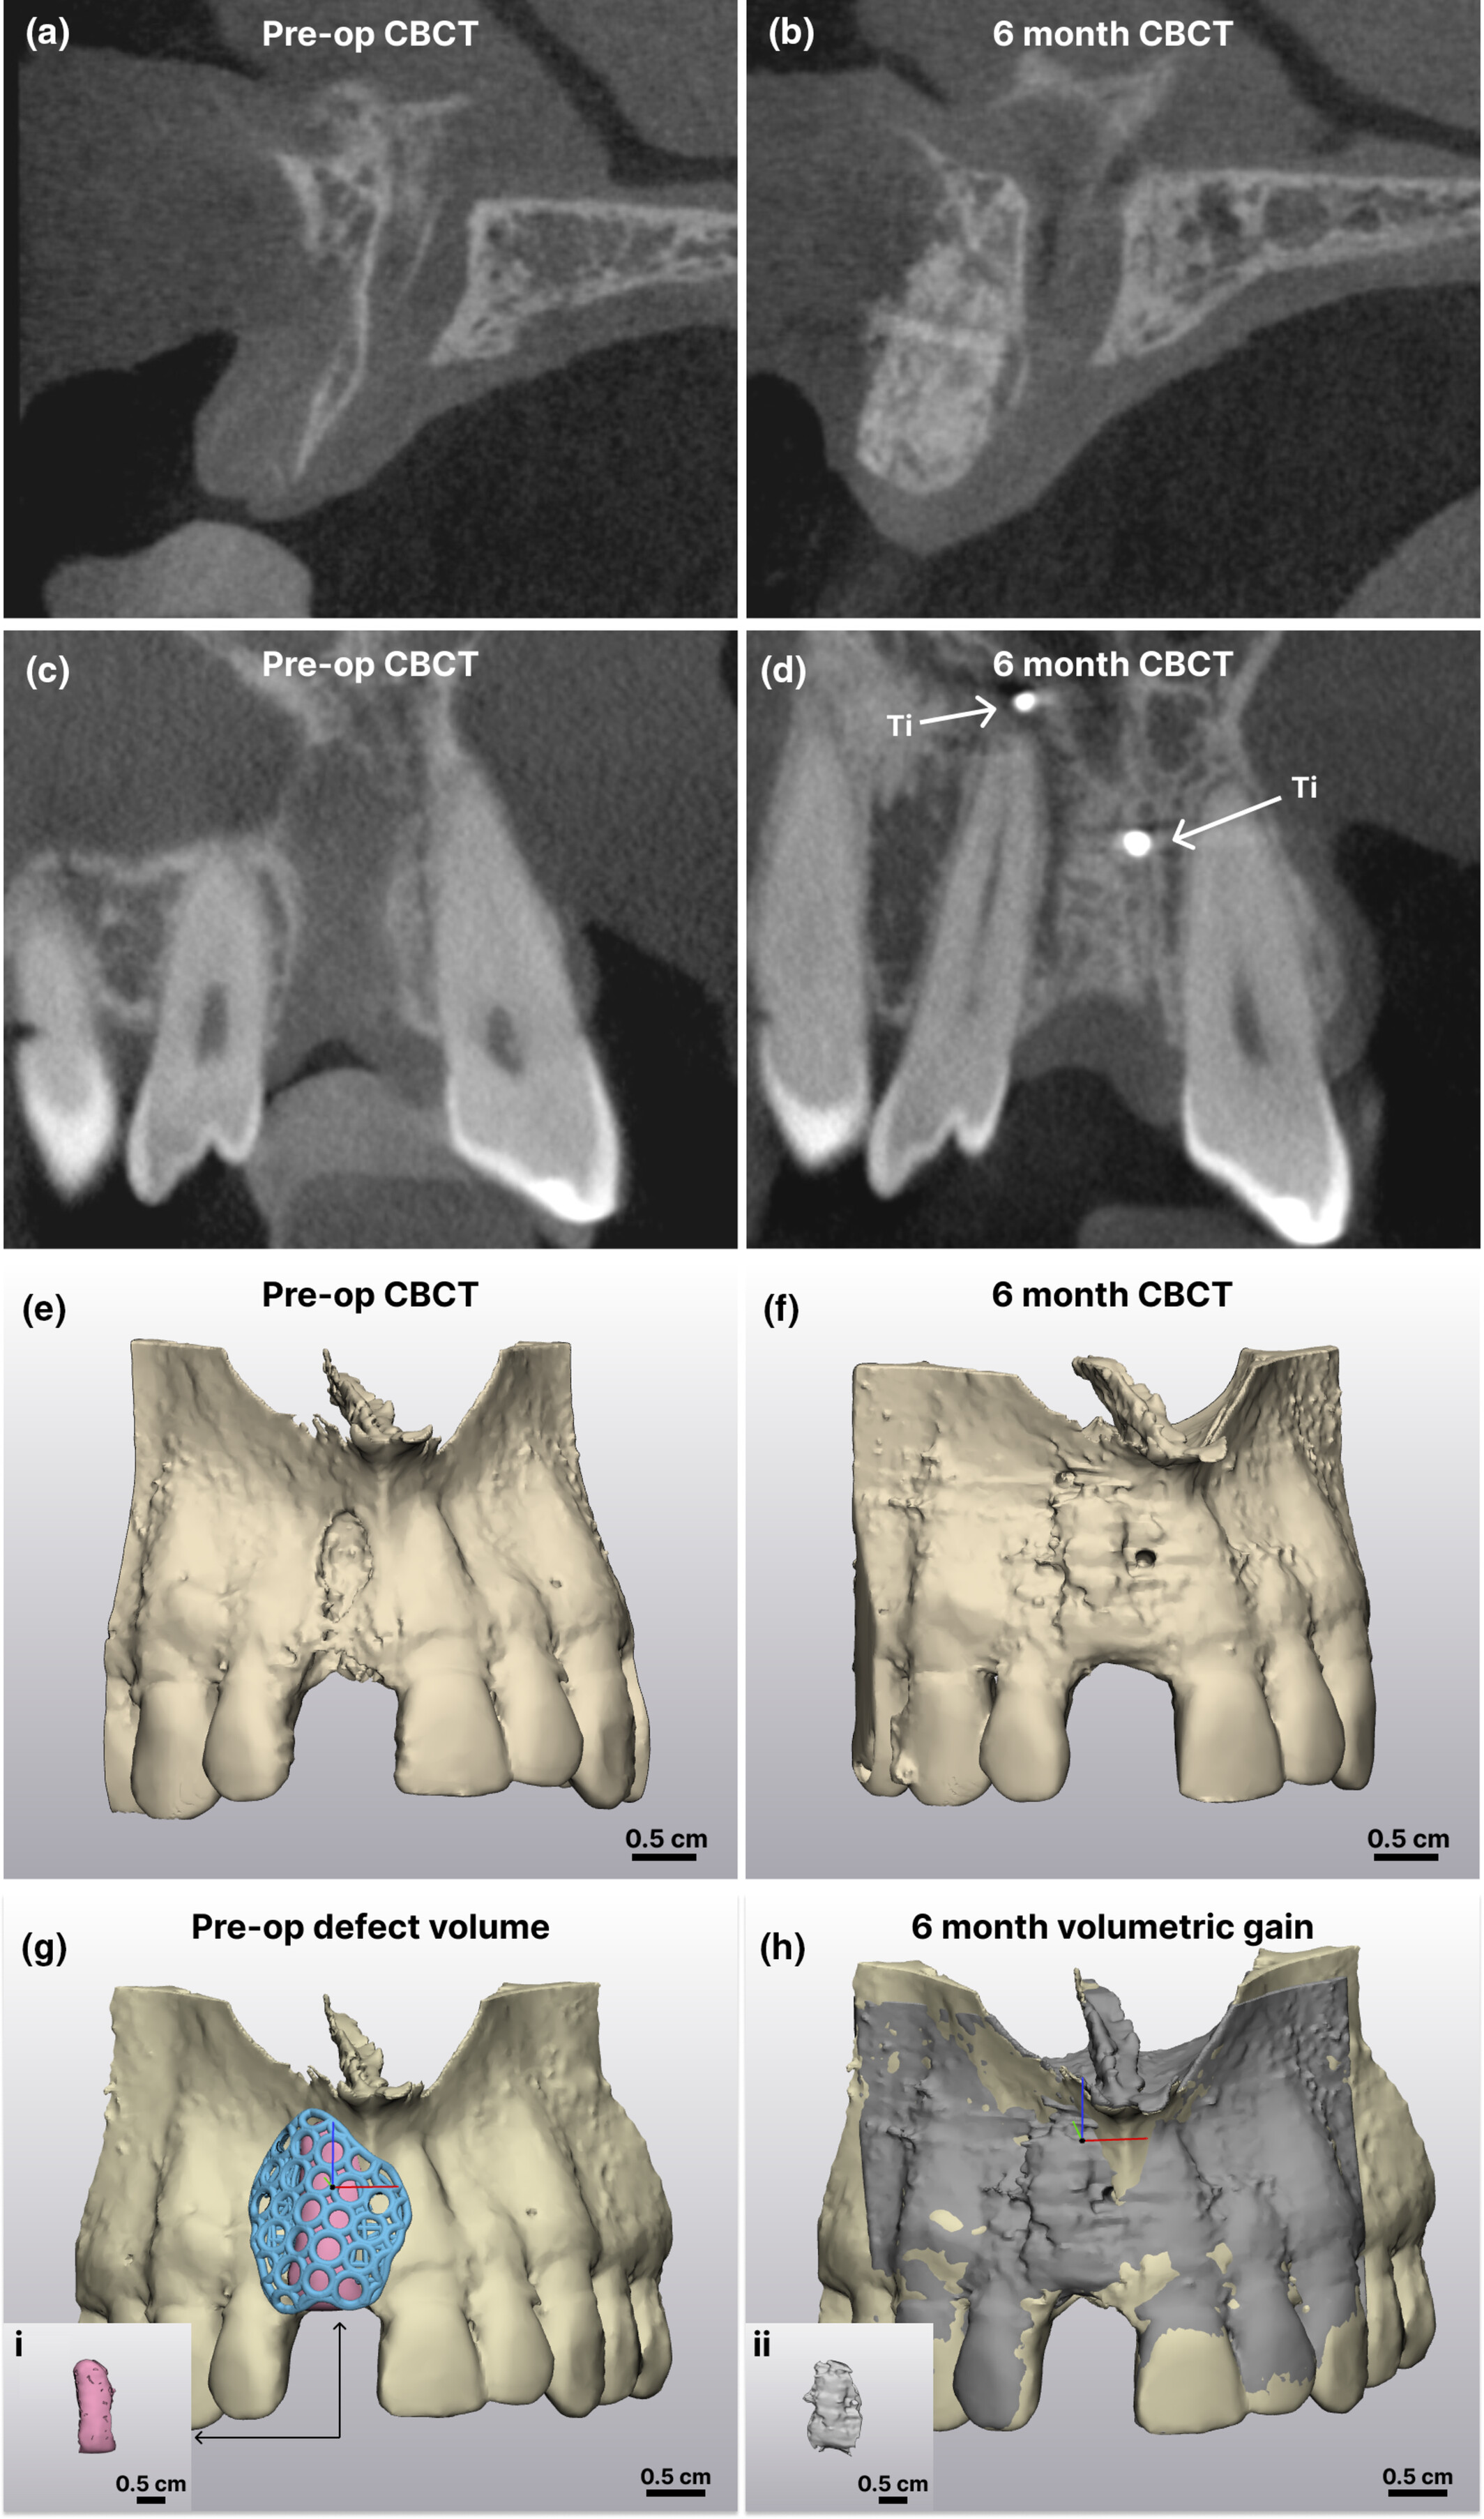

案例中患者术前 GBR CBCT 与 6 个月愈合后的X 射线图像比较。 (a 和 c) 术前矢状面和冠状面横截面;(b 和 d) 术后 6 个月矢状面和冠状面横截面;(e 和 f) CBCT 图像的 3D 重建(术前和术后 6 个月);(g) 术前缺损体积;Ti,钛固定螺钉;(i) 粉色体积代表支架下方没有骨骼的区域;(h) 6 个月体积增加;(ii) 灰色体积的分割代表通过布尔减法得到的术前和 6 个月 CBCT 之间的差异。比例尺 = 0.5 cm。